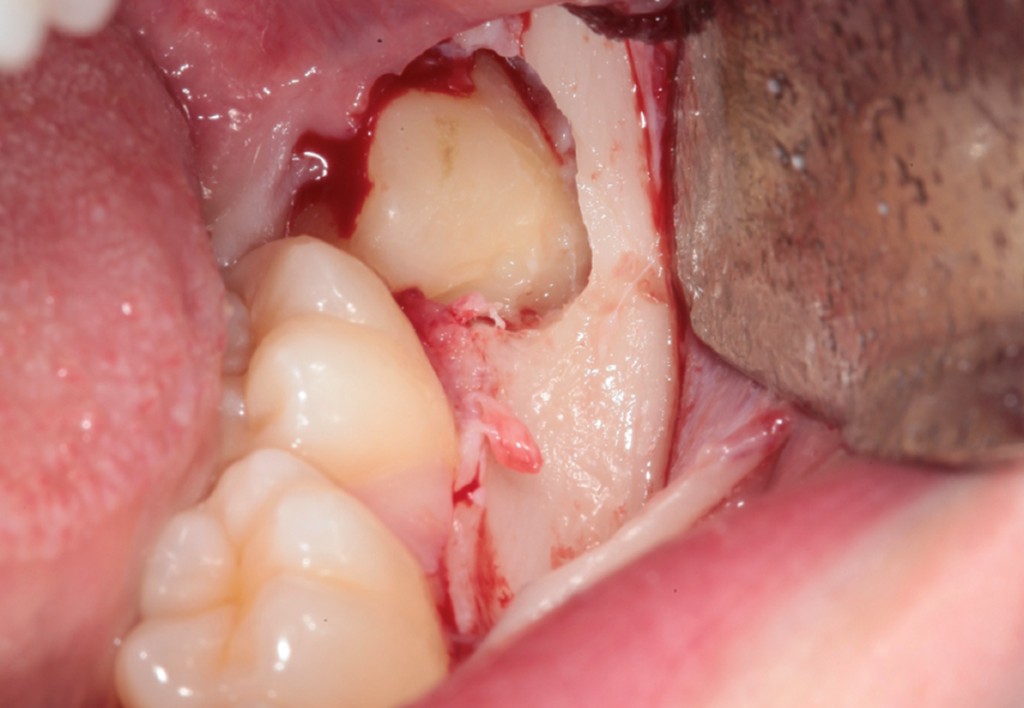

► Tecniche chirurgiche per elementi complessi

Approccio ad elementi inclusi, parzialmente inclusi, in arcata o sovrannumerari, con tecniche atraumatiche e sicure.

Galleria fotografica